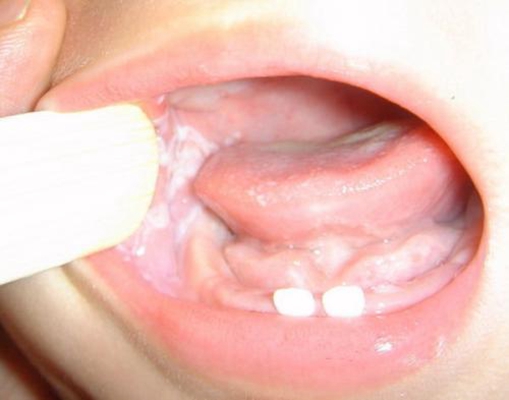

口腔念珠菌感染 (46)